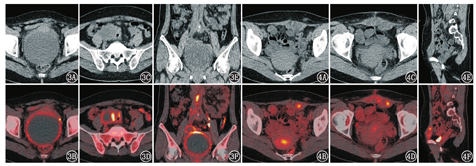

移位的卵巢生理性摄取需要与病理性情况相鉴别,同样地,异位的子宫内膜的生理性摄取也需要与恶性病变相鉴别。处在月经期的异位子宫内膜可以和月经期宫内的内膜一样,有生理性摄取增高(图2)。子宫内膜组织异位于卵巢可形成卵巢巧克力囊肿,也可广泛异位于腹盆腔,并且反复出血、形成纤维素性包裹,造成粘连、囊肿破裂,还可继发盆腔炎或盆腔囊肿,这种伴有活动性炎性反应的子宫内膜异位症也可表现为FDG代谢增高(图3)[7]。但需要注意的是,异位的子宫内膜有一定的恶变概率(约2.5%)[8],如恶变为卵巢透明细胞癌、子宫内膜样癌、低级别浆液性癌等,在PET/CT上难以鉴别(图4),需要进一步病理检查。